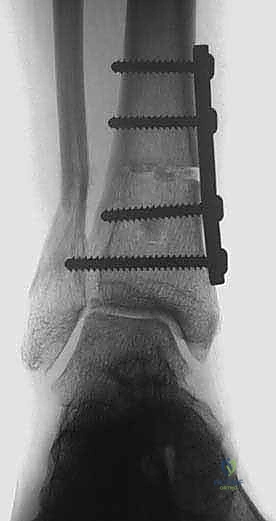

2. التصوير بالأشعة السينية بوضعية الوقوف (Weight-bearing X-rays)

هذا هو حجر الأساس في التشخيص. الأشعة العادية والمريض مستلقٍ لا تظهر الحجم الحقيقي للتشوه. يطلب الدكتور هطيف صوراً خاصة والمريض يحمل وزنه كاملاً على قدميه.

* المنظر الأمامي الخلفي (AP View): لتقييم المسافة المفصلية وتحديد زاوية سطح الساق (Tibial Anterior Surface Angle - TAS).

* منظر سالتزمان (Saltzman View): وهو منظر إشعاعي متخصص جداً لتقييم محاذاة الكعب الخلفي بالنسبة لمحور الساق، وهو أمر حاسم في التخطيط الجراحي.

التخطيط الجراحي: دقة المليمتر مع الدكتور محمد هطيف